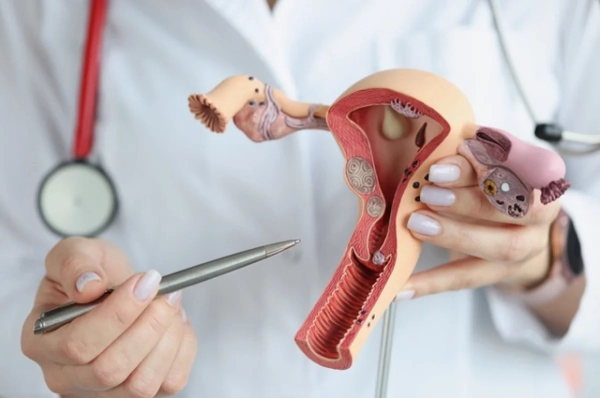

istockphoto.com Врачи из благотворительной некоммерческой организации в Великобритании Robin Cancer Trust рассказали о ранних признаках онкологии яичников,...